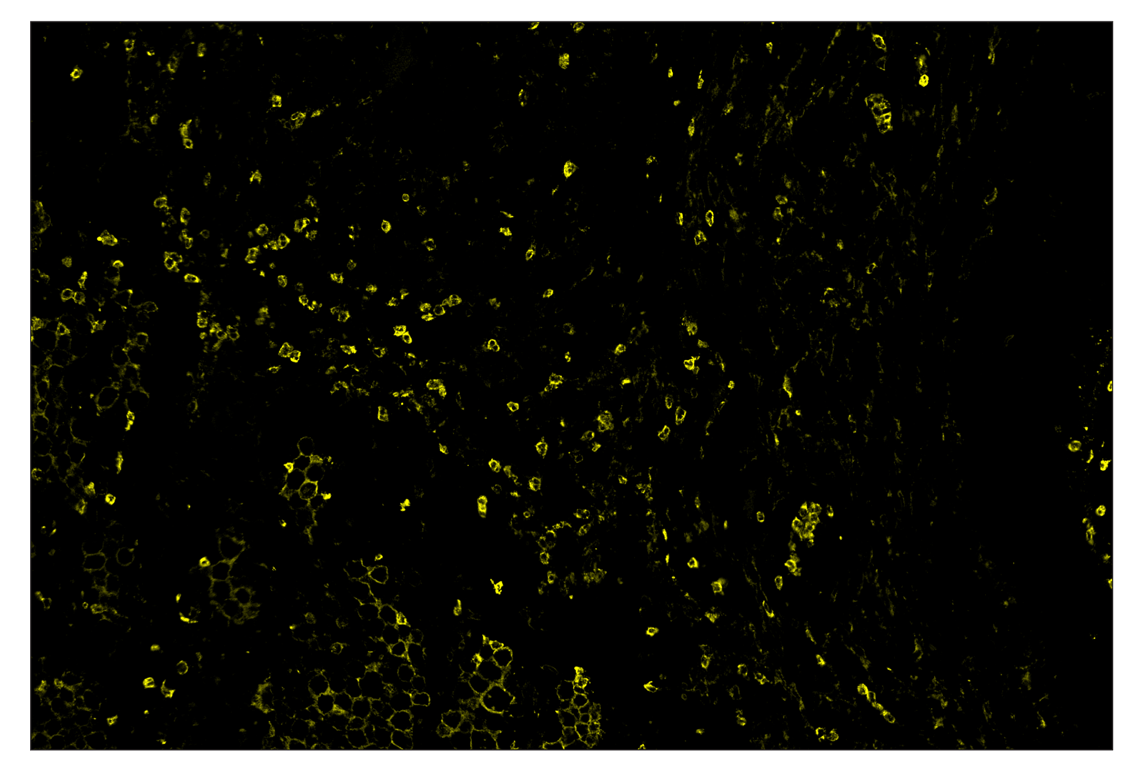

SignalStar™ immunohistochemical analysis of paraffin-embedded human squamous cell lung carcinoma using CD11b/ITGAM (D6X1N) & CO-0037-594 SignalStar™ Oligo-Antibody Pair #96835 (yellow). All fluorophores have been assigned a pseudocolor, as indicated. Staining was performed on the BOND RX autostainer by Leica Biosystems.

Immunohistochemistry Image 3: CD11b/ITGAM (D6X1N) & CO-0037-488 SignalStar<sup>™</sup> Oligo-Antibody Pair